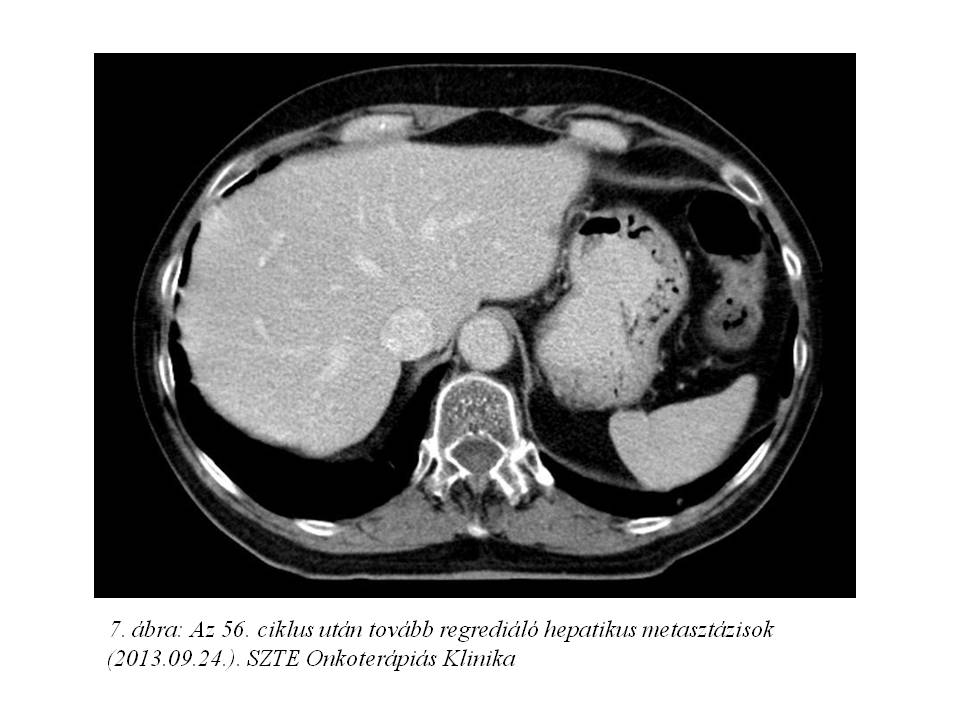

Az 56. ciklus FOLFIRI-bevacizumab immuno-chemotherápiát 2013.09.24-én adtuk, mely utáni CT vizsgálaton (7. ábra, 8. ábra) 80%-os regressziót láttunk az alapvizsgálathoz képest, azonban novum lyticus és scleroticus átépülés jelent meg a jobb csípőlapátban, mely felvetette csontmetasztázis lehetőségét. Ezt egy friss csontscintigráfiás lelet (9. ábra) is megerősítette, és a beteg fokozódó csípő és hátfájdalmai is ezt támasztották alá. Az ossealis propagatio miatt elsővonalas terápiáját felfüggesztettük, fájdalomcsillapítás céljából palliatív irradiatio történt 2013.11.26-tól, a metasztatikusan érintett lumbális IV-V. csigolyákra és medencecsontokra (jobb os ileum, acetabulum), 10x3 Gy frakciódózissal. (10. ábra). Ezen kívül biszfoszfonát (4 mg zoledronsav iv., q4w) kezelés is indult.